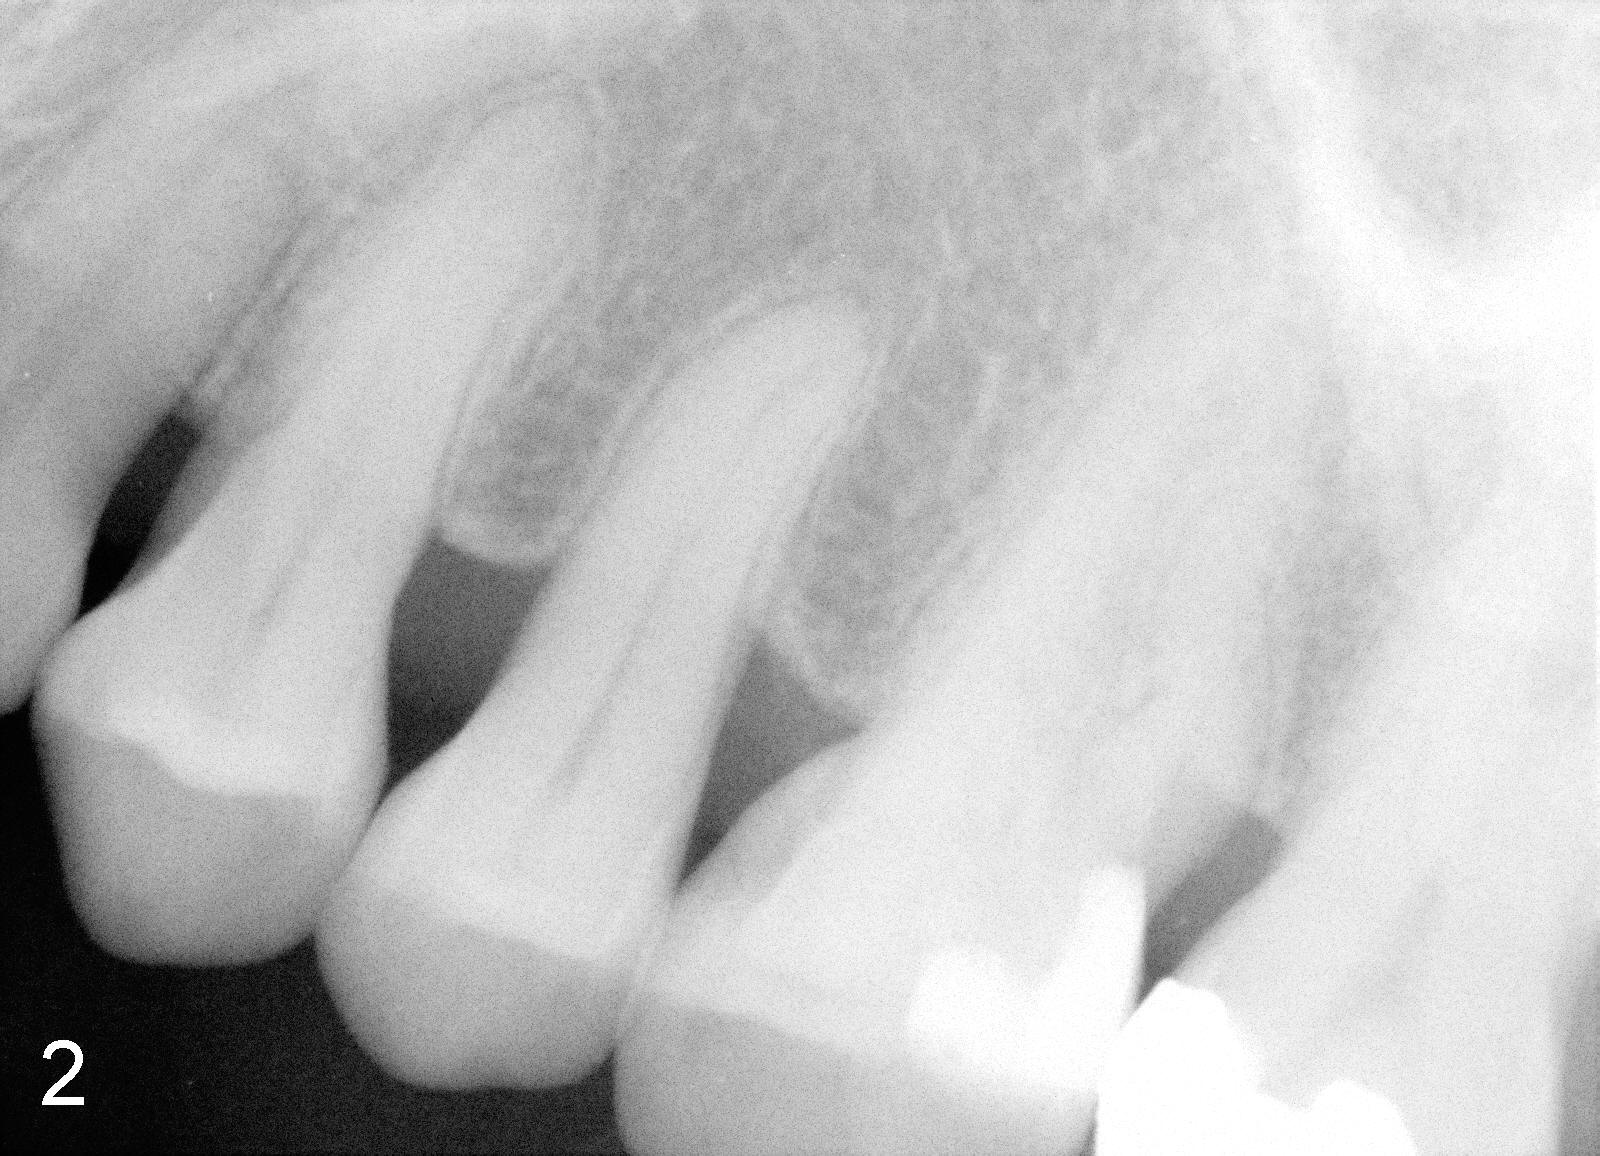

Bitewing and PAs for Upper Left Quadrant

X-ray was taken on 01/18/2010 (Fig.1) and 06/11/2011 (Fig.2-4). Clinically there is no gross lesion in the upper left quadrant, although pain is vague in position, according to the patient.

I think you have done a remarkable job. The mesial root is untreatable with the furcation and poor oral hygiene. I would advise the patient to keep cleaning the area with small brush and irrigate with salt water to furcation area. If pain persist and become intolerable, advice patient for extraction. I don't think she needs to see me at this time.